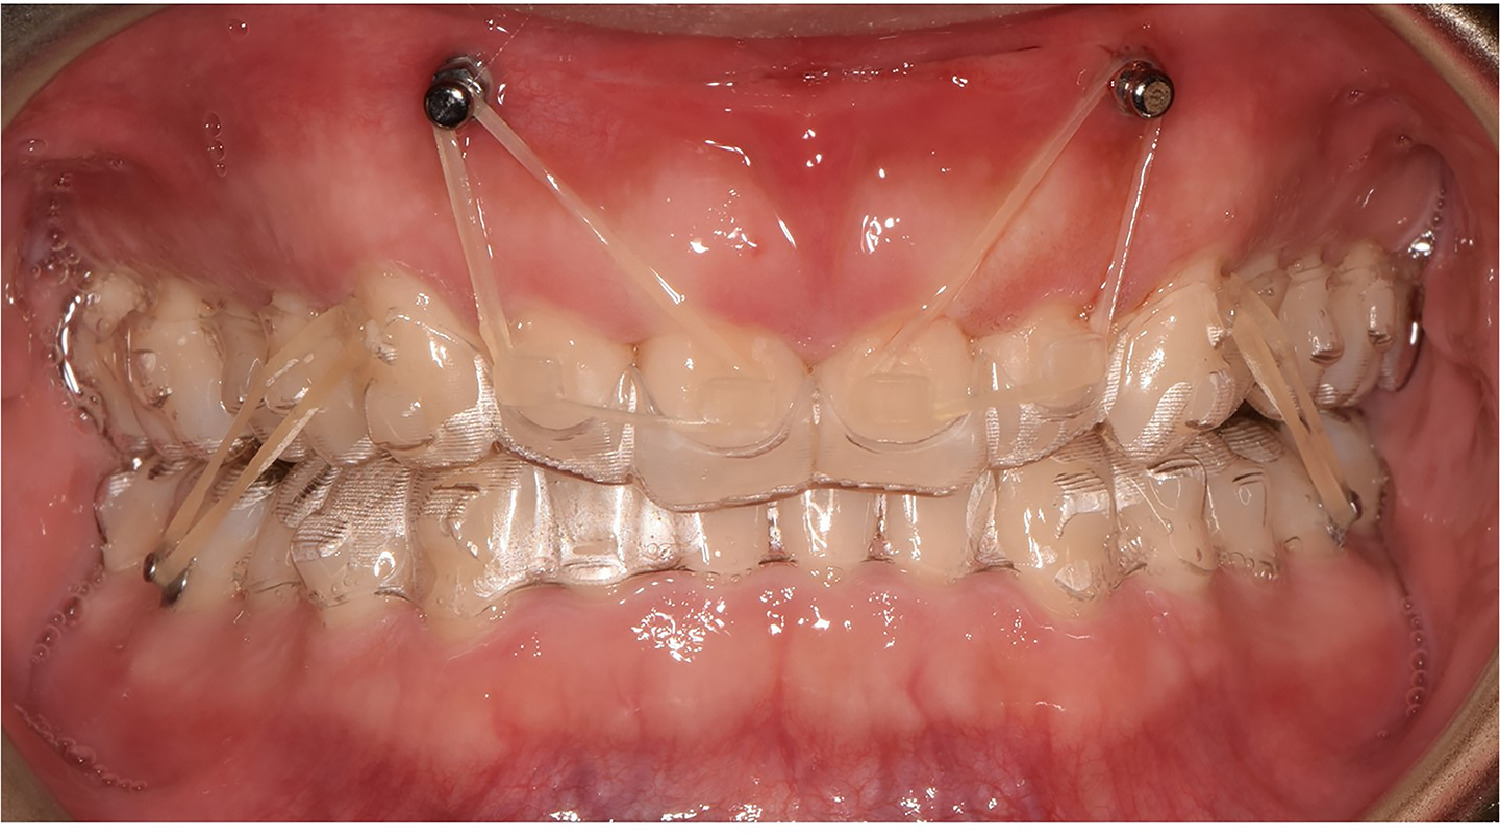

Orthodontic TAD mini-screw placement in clinic by Dr Benguira

Connection to brackets or aligners via elastics or springs. The mini-screw works silently 24/7.

Connected to brackets or aligners via elastics or springs, it exerts a constant and controlled force.